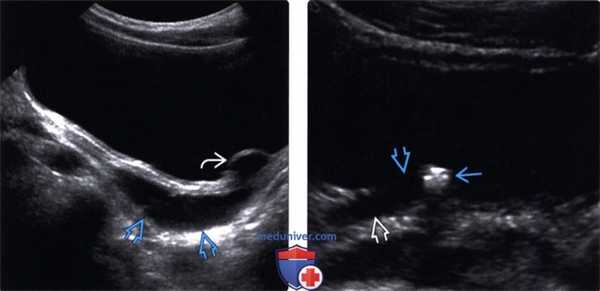

(Левый) На продольном трансабдоминальном УЗ срезе визуализируется небольшое уретероцеле с восходящей дилатацией мочеточника.

(Правый) На косопоперечном трансабдоминальном УЗ срезе визуализируется гиперэхогенный конкремент, вдавленный в правый пузырно-мочеточниковый сегмент (ПМС) с восходящей дилатацией мочеточника. Локальное выпячивание в интрамуральном отделе мочеточника соответствует псевдоуретероцеле.